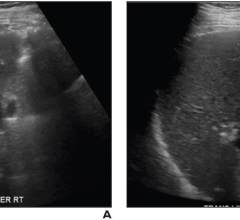

Ultrasound uses sound waves to create images. This section includes breast ultrasound, echocardiography (echo), transthoracic echo (TTE), transesophageal echo (TEE), echo contrast, transducers, ultrasound software and point-of-care ultrasound (POCUS).

The most common cause of chronic liver disease? Nonalcoholic fatty liver disease (NAFLD). With 25% of the world’s ...